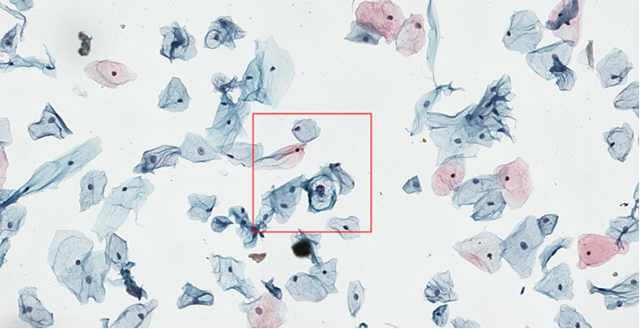

低度鳞状上皮内病变细胞(LSIL)

据汤红平介绍,在宫颈癌筛查中,一张切片上有时多达数万个细胞,医生单纯用人眼去判读不仅耗时长,还可能会造成遗漏。当运用人工智能手段后,AI系统可快速判断细胞图像数据,让切片里的每一个细胞都得到检测,并呈现出可疑细胞,再由医生进行确认。这样可以大幅提高诊断效率和检测敏感度,更加高效精准地进行临床诊疗。